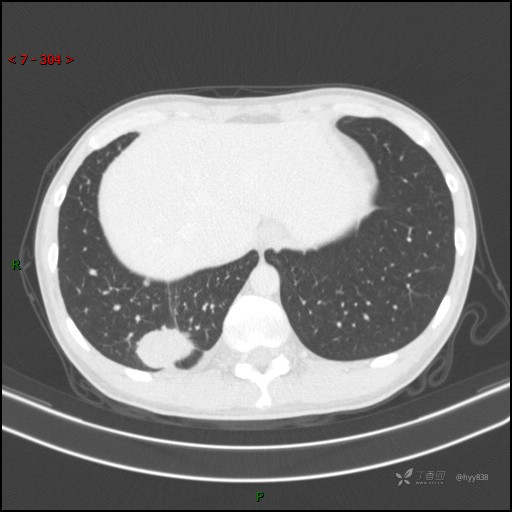

胸部CT平扫